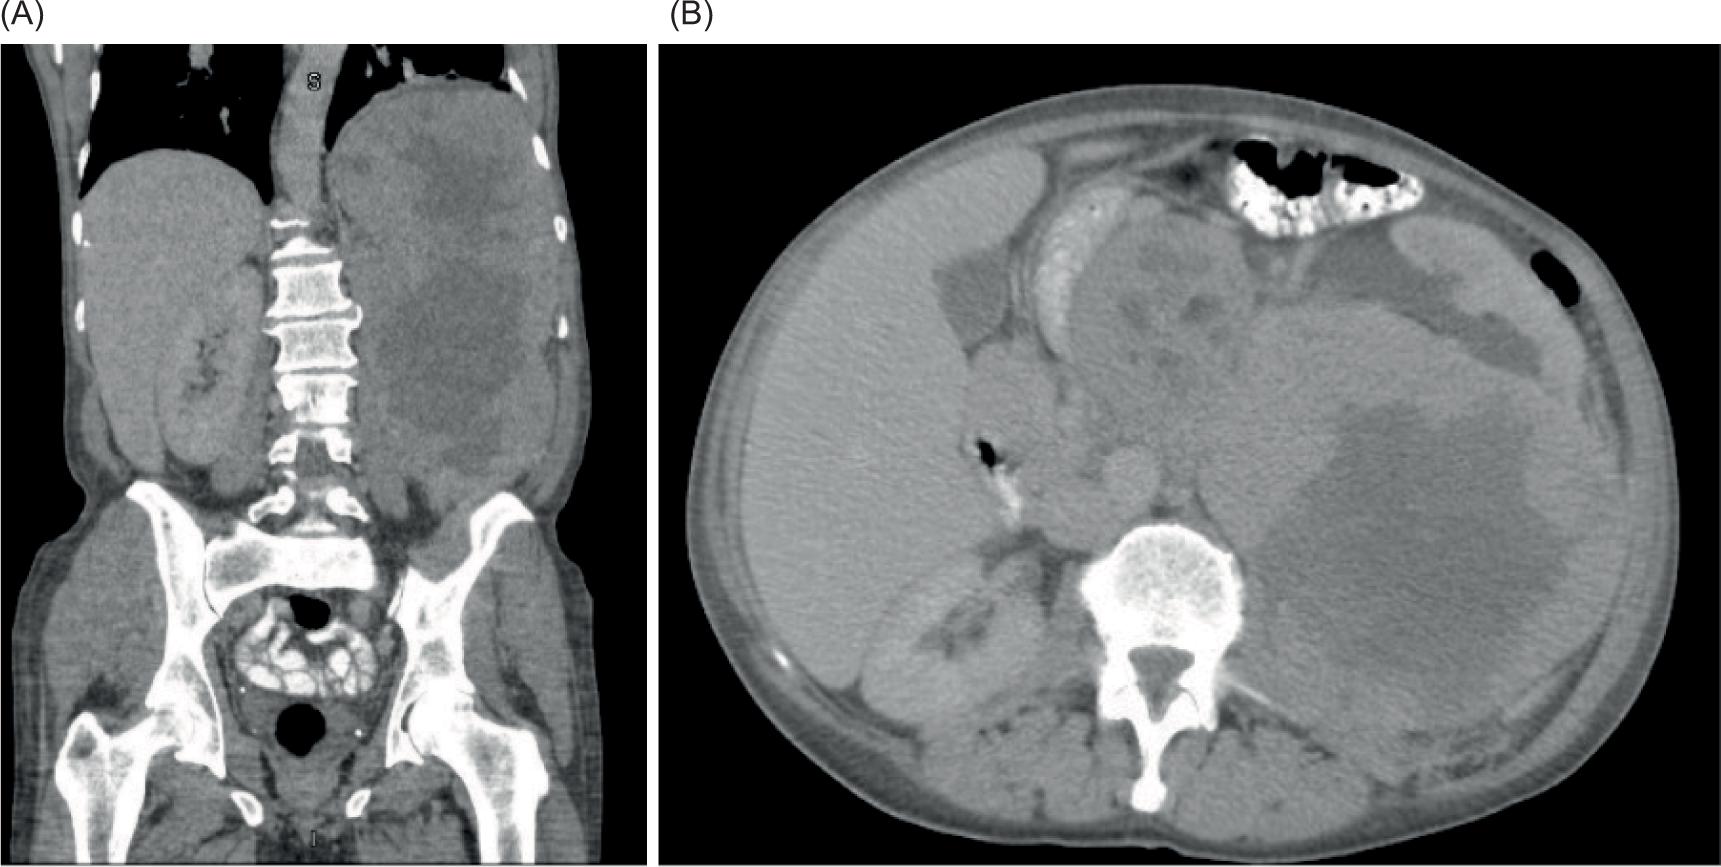

A 57-year-old man presented to his pulmonologist with worsening headaches and sinus congestion. This ultimately prompted computed tomography (CT) imaging which revealed a small left lung effusion, two nodules of the right lung, left hemidiaphragmatic elevation, and a 20-cm centrally necrotic neoplasm in the left upper quadrant (Figure 1). Positron emission tomography (PET) re-demonstrated the retroperitoneal mass, measuring 30 × 16 × 11 cm with a standardized uptake value (SUV) of 7.0, suggestive of malignancy. One fine-needle aspiration (FNA) sample and four core needle biopsy samples were obtained, revealing a malignant PEComa. Magnetic Resonance Imaging (MRI) demonstrated no brain metastases. However, further axial imaging revealed pelvic adenopathy and multiple pulmonary nodules, indicative of metastatic disease.

Figure 1: Abdominal CT images with contrast. CT images of the abdomen in coronal (A) and axial (B) planes with contrast enhancement demonstrating a large left retroperitoneal mass.